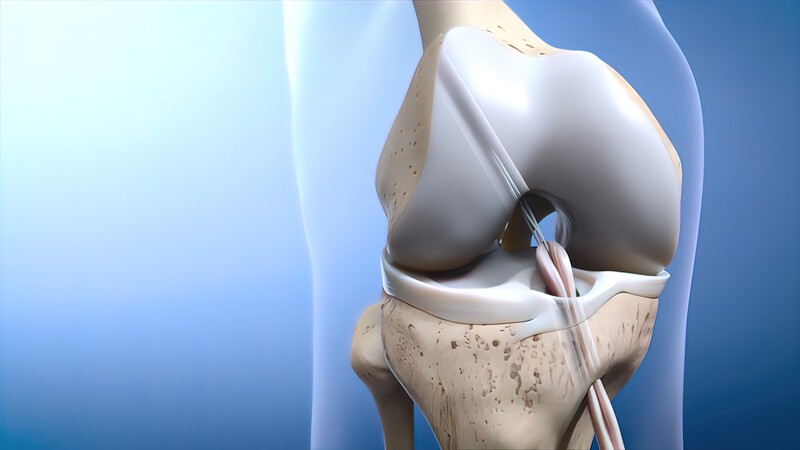

Arthoscopic Surgery

Arthoscopic surgery or key hole surgery allows the surgeon to address multiple problems with the shoulder & knee joint like ligament or tendon tear without actually opening the joint. It requires the need of specialised equipment & a trained surgeon to perform the surgery & give good results

Knee Arthroscopy

Knee arthroscopy, also known as keyhole knee surgery, is a minimally invasive surgical procedure used to diagnose and treat a variety of knee conditions. It involves the use of a small camera (arthroscope) and specialized instruments inserted through tiny incisions in the knee to visualize and address issues within the joint. Knee arthroscopy has become a common and effective method for managing a wide range of knee problems, from diagnosing unexplained knee pain to repairing damaged ligaments and cartilage.